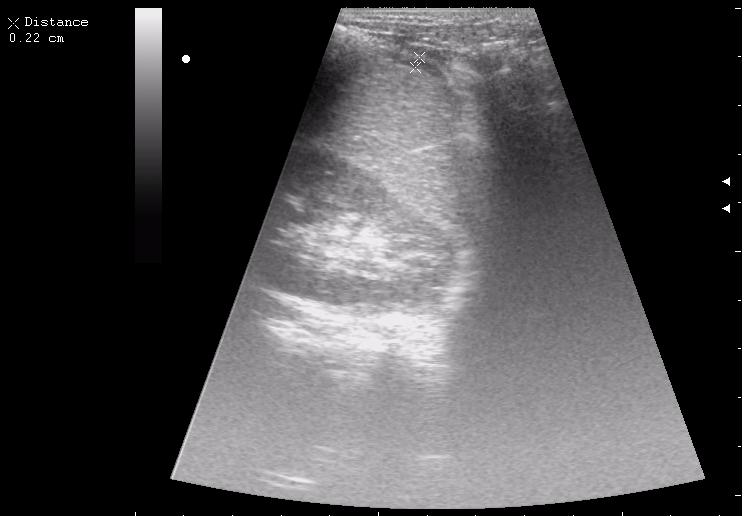

железный дрын вошел в правую подвздошную область, остановился в капсуле печени.

наезд большой черной Прады на маленькую (13кг) 5-летнюю девочку.

получает Медаксон, рабочая версия - изменение желчного пузыря вследствии травмы (шепотом - рекомендация хирургу сменить антибиотик)